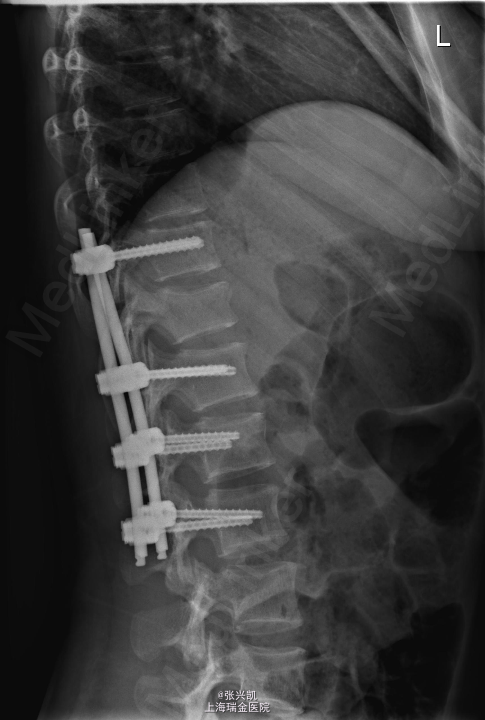

诊断:多发胸腰椎骨折(T11,L1) 处理:胸腰椎骨折经皮椎弓根钉复位内固定术,一年后骨折愈合良好,行内固定装置取出术

随访:术后三月复诊,内固定装置位置良好,患者腰背痛症状缓解,一年后骨折愈合,行内固定装置取出。术后患者腰部活动良好 讨论:术后应积极锻炼腰背部肌肉,防止萎缩。